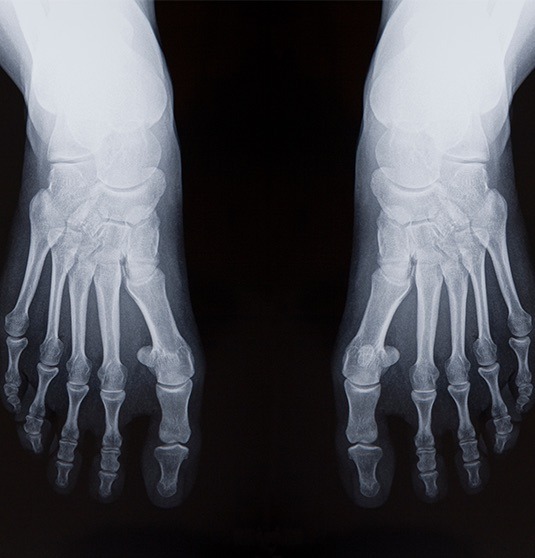

Ein Spreizfuss kann einen oder beide Füsse betreffen und verursacht oft Probleme und Symptome, die den Alltag und die Lebensqualität beeinträchtigen. Unbehandelt kann sich die Fehlstellung des Fusses auf den gesamten Körper auswirken.